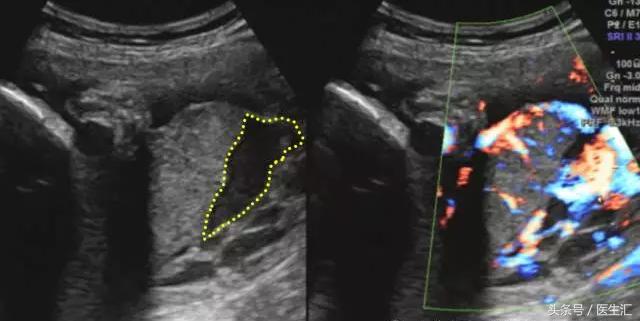

1.胎盘内血池或血窦:位于胎盘实质内,在胎盘切面内呈不规则液性暗区,内有云雾状回声呈沸水征。(见图2黄色圈内)

图2,胎盘左侧缘及右侧缘后方与宫壁间均见条状无回声区,范围约:40mm×14mm(左侧缘),36mm×9mm(右侧缘),内见密集光点浮动,似可探及静脉血流信号。